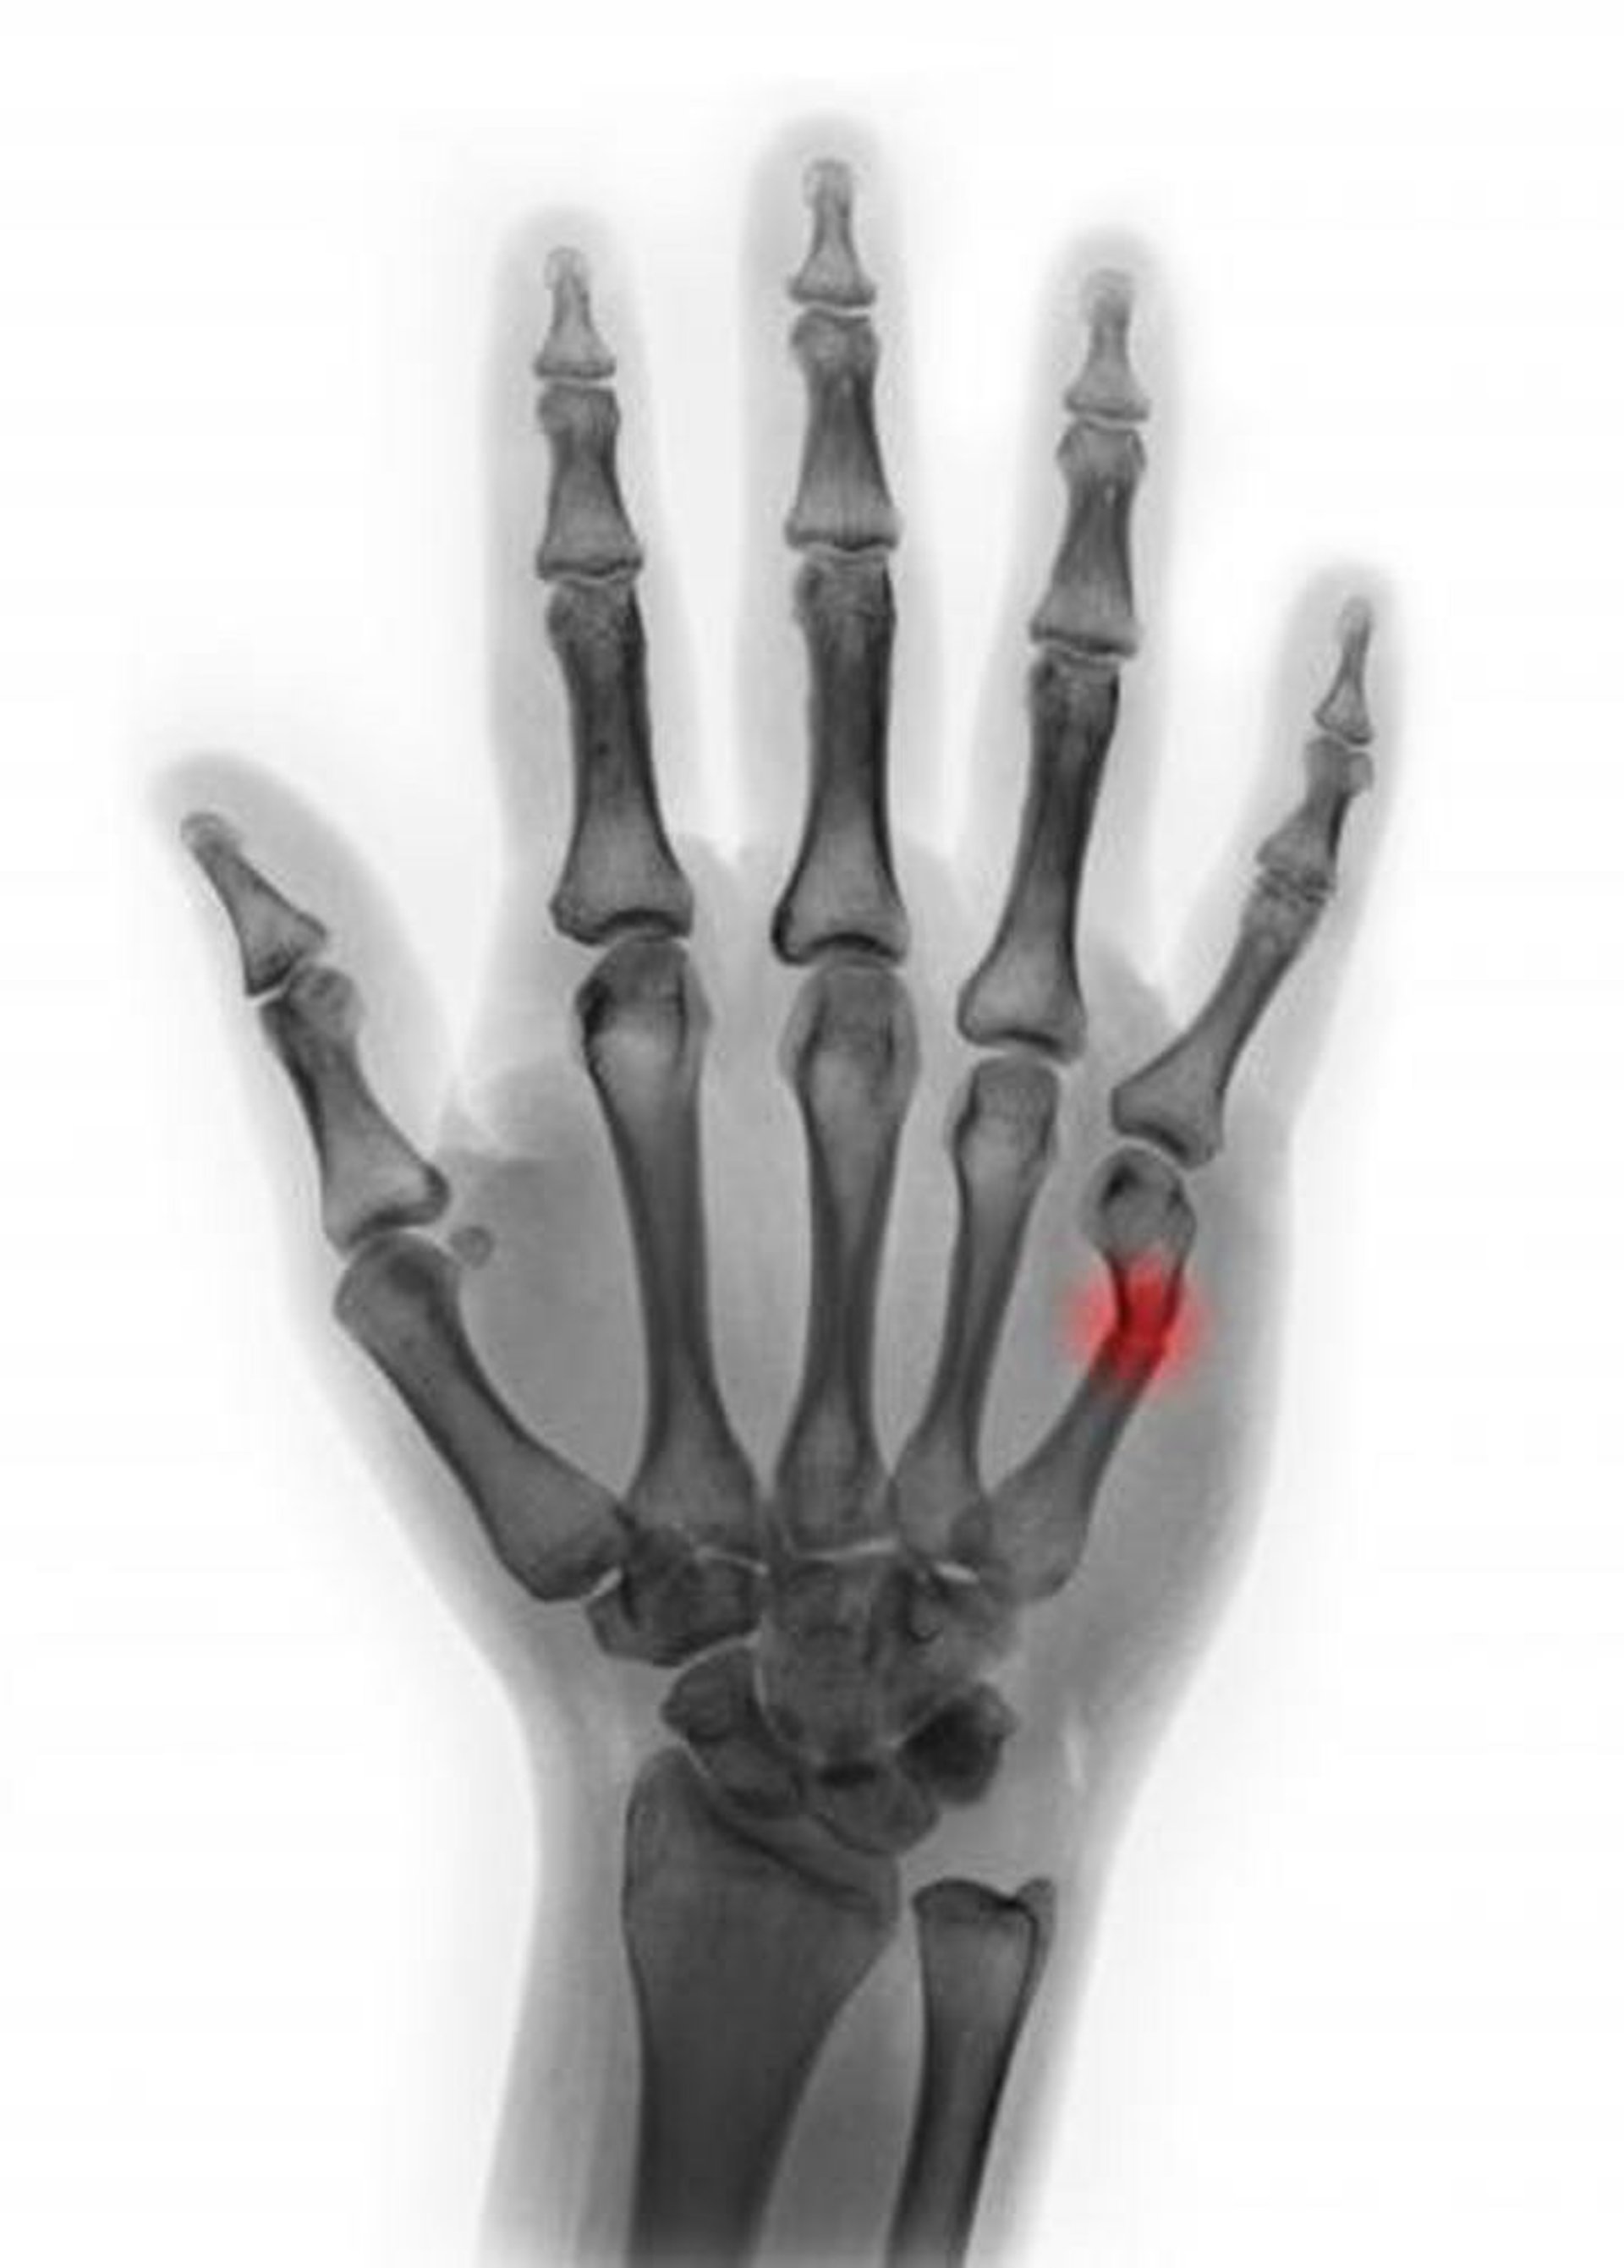

Fracture du col du 5e métacarpien

Cette radiographie colorée montre une fracture du col du 5e métacarpien. Dans cette vue, l'angulation semble être < 45°, ce qui suggère que la réduction n'est pas nécessaire.

SCOTT CAMAZINE/SCIENCE PHOTO LIBRARY